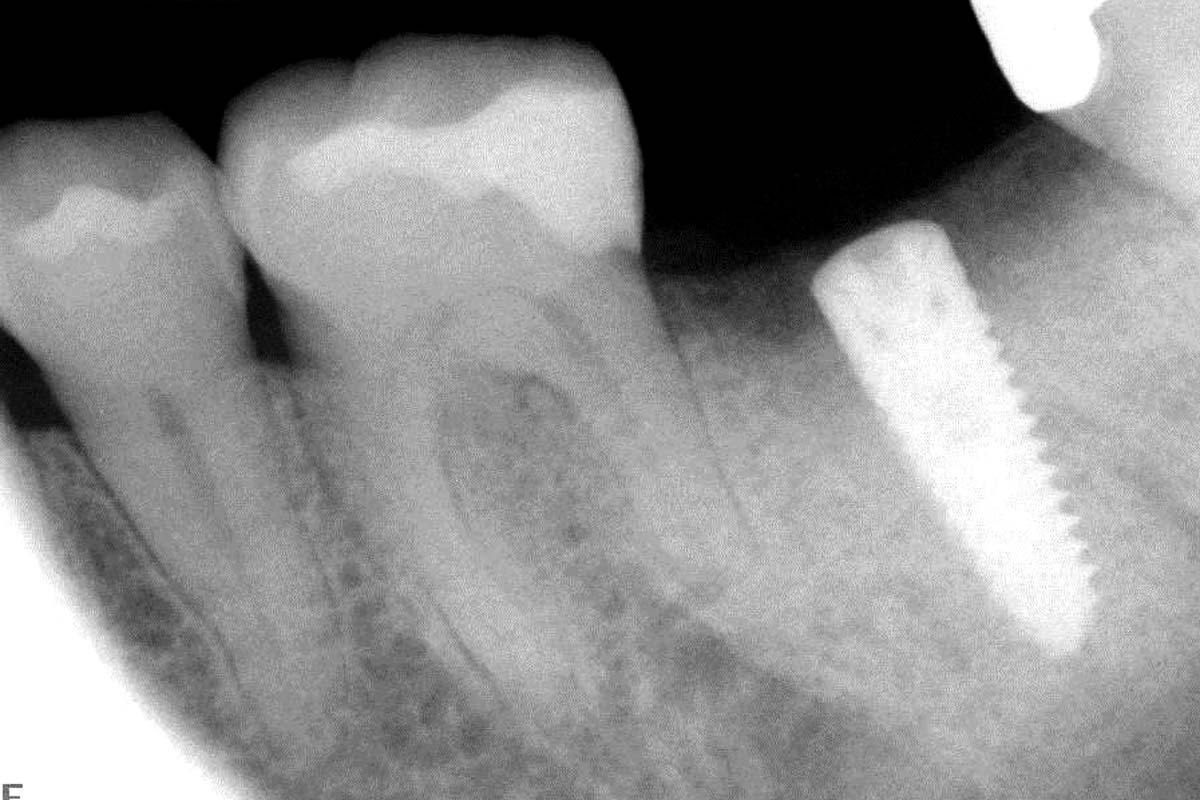

Instable bridge situation with abscess formation at tooth #15 after apicoectomy